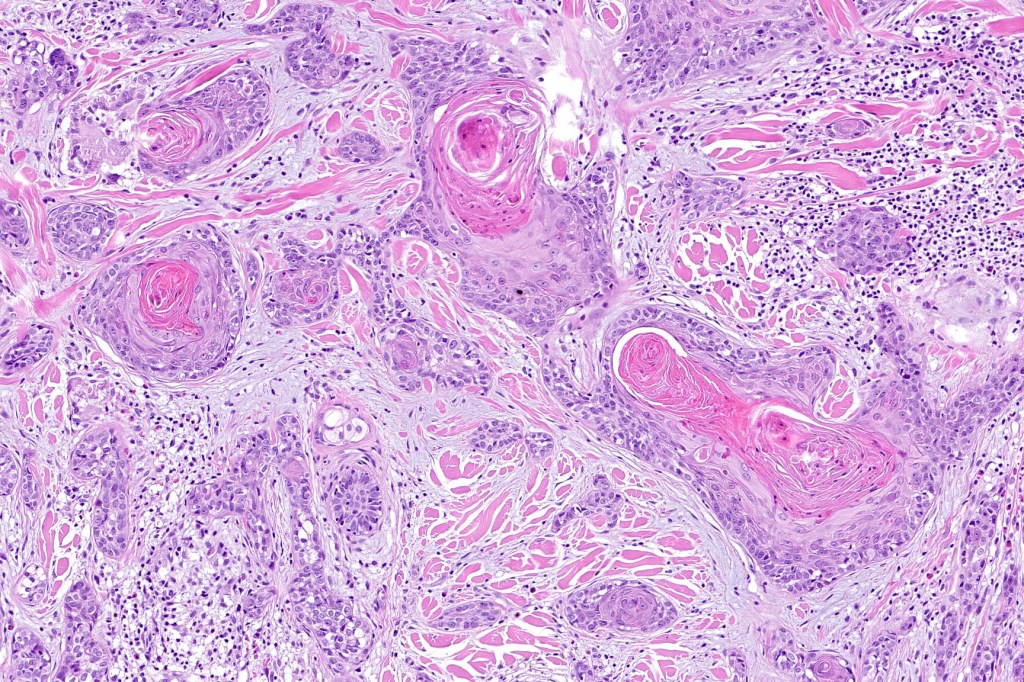

•Adenocarcinoma in deeper reaches

•Variable pleomorphism and mitotic activity

•Deep part may show both ducts and glands

•Perineural infiltration is commonly seen